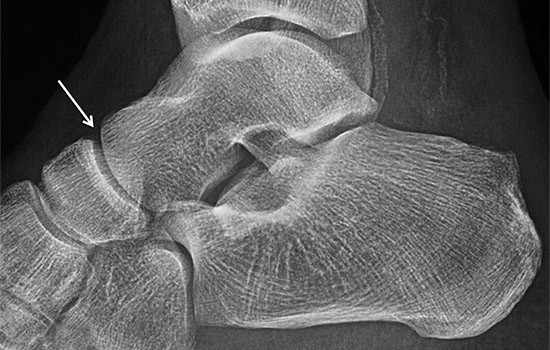

El estudio de imagen con rayos X es suficiente para identificar el problema y confirmar el diagnóstico de la artrosis Astrágalo Escafoidea. Es recomendable la realización de radiografías dorsoplantar, lateral y oblicuas de los pies, las dos primeras proyecciones en carga.

Rx Lateral. Artrosis Astragalo-escafoidea

Radiografía Lateral. Artrosis Astragalo-escafoidea